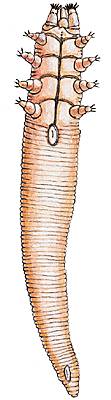

On connaît environ 7 000 espèces d'acariens. Leur taille, généralement égale ou inférieure à 1 mm (aoûtat, sarcopte de la gale), peut dépasser 1 cm chez les tiques. Les acariens sont les plus évolués des arachnides.

Les mâles, souvent nettement plus petits que les femelles, possèdent parfois des organes copulateurs, mais la plupart utilisent leurs « pattes-mâchoires » ou leurs pattes pour féconder les femelles. Le développement du jeune passe par une série de stades larvaires et nymphaux, au cours desquels la morphologie de l'animal se modifie considérablement.

Parmi les acariens ectoparasites (vivant sur la peau) de l'homme, certains ne provoquent que des désagréments cutanés, comme des démangeaisons : rouget, ou aoûtat, démodex, sarcopte de la gale. D'autres, telles les tiques, qui sont hématophages (elles se nourrissent du sang de leur hôte), transmettent des maladies infectieuses : arboviroses (diverses fièvres virales), rickettsioses (fièvres pourprées), fièvre Q, borrélioses (fièvres récurrentes, maladie de Lyme).